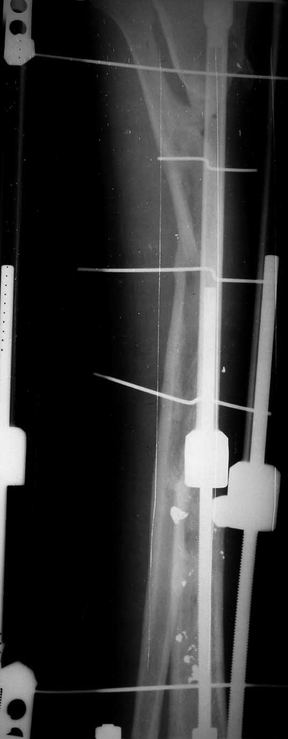

Отправлено Ласунский Сергей 30 Октябрь 2007, 23:53 РОСНИИТО им.Р.Р.Вредена

Пациентка с дефектом большеберцовой кости, возможно ли восстановление опороспособности нижней конечности? ДТП 1.5 года назад: открытый оскольчатый перелом средней трети левой голени с дефектом мягких тканей. Выполнены следующие операции в одной мз больниц города: 1.При поступлении ПХО и наложение АВФ 2.Нагноение резекция нежизнеспособной кости. 3.Пластика дефекта мягких тканей. 4.Попытка устранения дефекта по методу Илизарова, нагноение, радикальная хирургическая обработка, увеличение дефекта. 6 месяцев без признаков гнойного воспаления. В настоящее время иммбилизация гипсовой лонгетой до коленного сустава, функция коленного сустава сохранена, голеностопного нет.

Уважаемый Александр! Привет из Питера. Спасибо за быстрый ответ. Стержень с блокированием и кейдж, вариант изветный по литеоатуре, но очень короткий дистальный фрагмент и локальный остеопороз (будет ли хорошая фиксация?). Как считаешь вариант с фиксацией ложного сустава малоберцовой кости спластиной и ее предварительное утолщение свободным аутотрансплантатом 1\2 малоберцовой кости со здоровой стороны длиной 20-25 см., а после консолидации тибиализация малоберцовой кости?